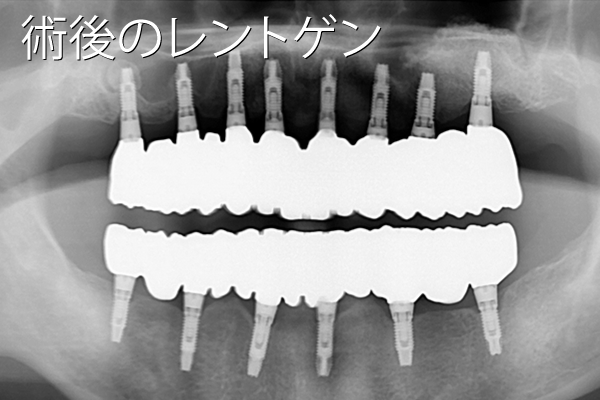

- 性別年齢

- 男性:55歳

- 治療内容

- 上顎に8本、下顎に6本のインプラント治療

- 金額

- 770万円(税込)

- 来院理由

- 歯周病が進行してきて噛めないし、口臭もひどい。専門医にインプラント治療について相談したい。

- 施術の

副作用

(リスク) - 経過とともになくなりますが、術直後に腫れや違和感を感じることがあります。